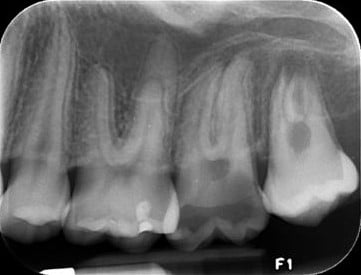

Descripción de imagen

Radiografías Periapicales

Realizamos toma de radiografías periapicales con la más alta calidad y precisión.